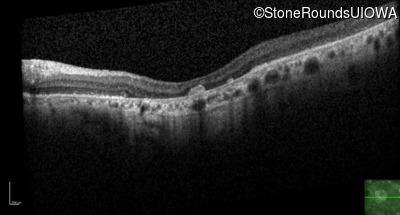

Optical Coherence Tomography - Right - 20/80

Exemplar / OCT Stack

OCT Stack